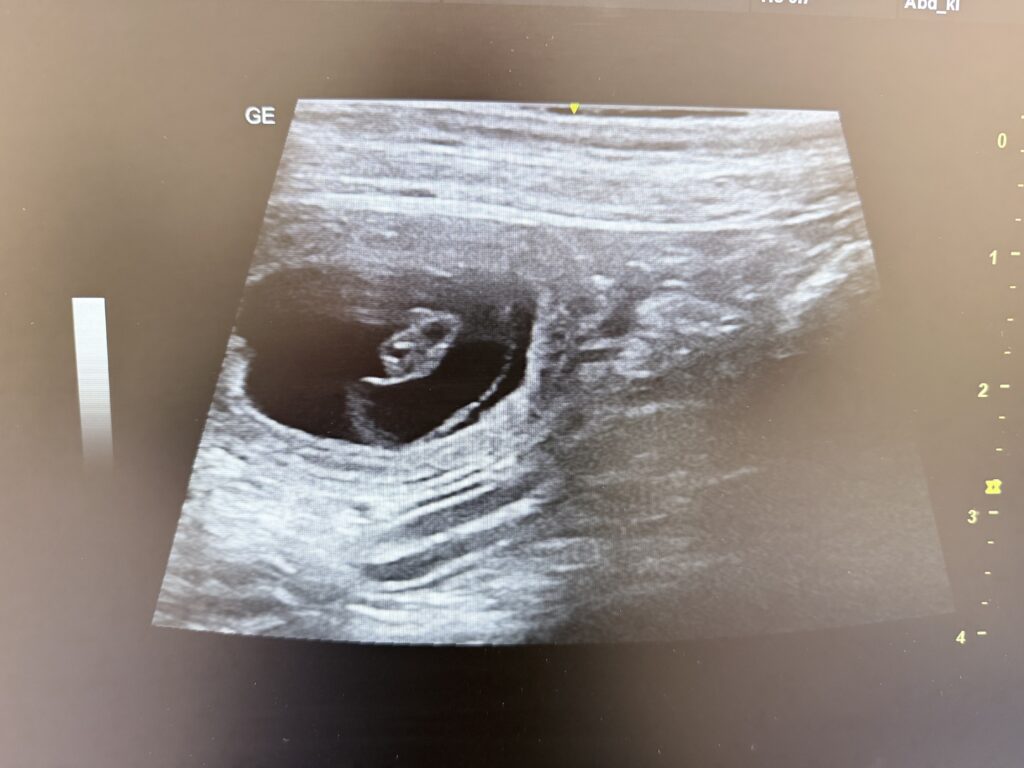

Wir erwarten Ende Februar Welpen aus Yuri vom Schinkelberg und Dabbi vom Rothenhausener Feld

Wir erwarten Mitte Mai Welpen!

Aus Aue vom Hevenbruch und Ravnalens Cafu.